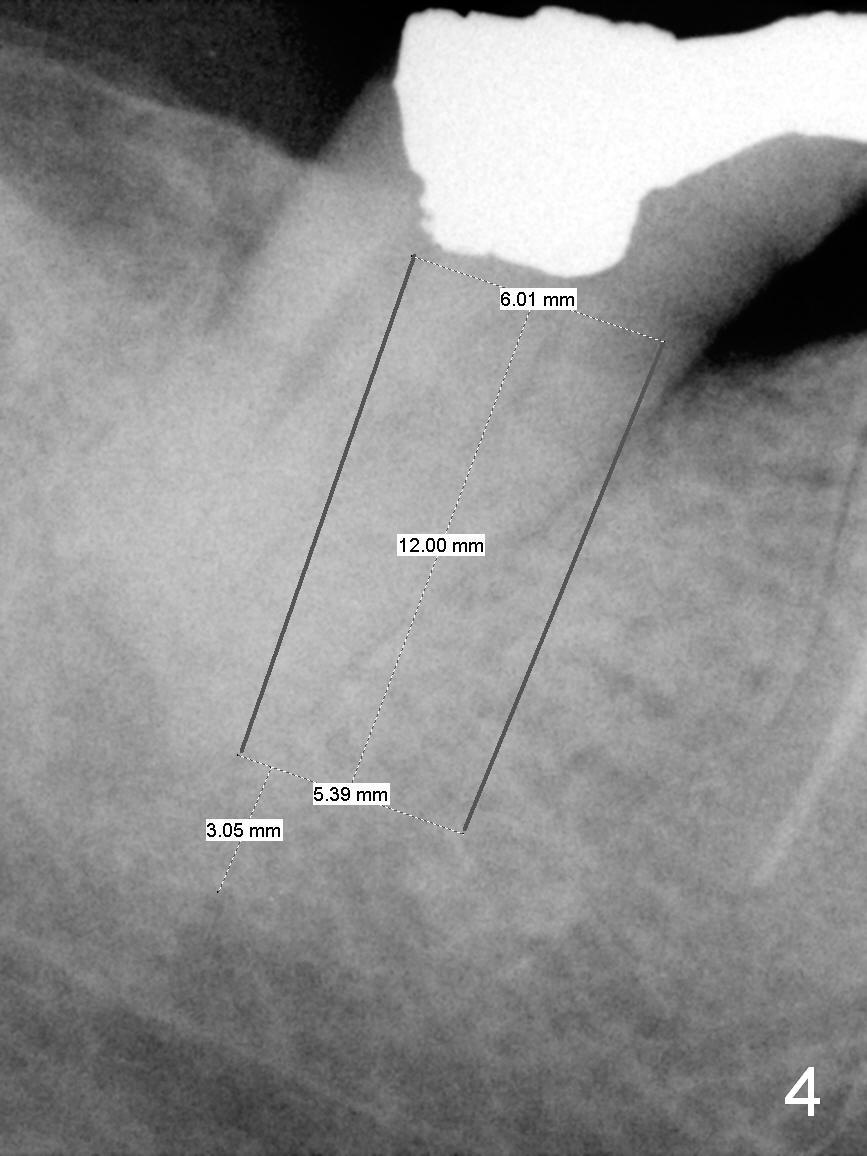

Where to Start Osteotomy? A 45-year-old lady (FY) has mild discomfort at #31 (Fig.31). Periapical radiolucency (Fig.2 arrowheads) is closely associated with the Inferior Alveolar Canal (red dashed line: upper border). Be careful when removing periapical granulation tissue. The socket will be treated with Clindamycin. If there is no severe pain associated with granulation tissue removal, osteotomy can be initiated lingual to the apex. An implant will be placed along the original long axis of the tooth (Fig.3). Otherwise, an implant will be placed in the mesial slope (Fig.4); the implant will be 2 mm longer; the upper end should be in the middle of the socket. Return to